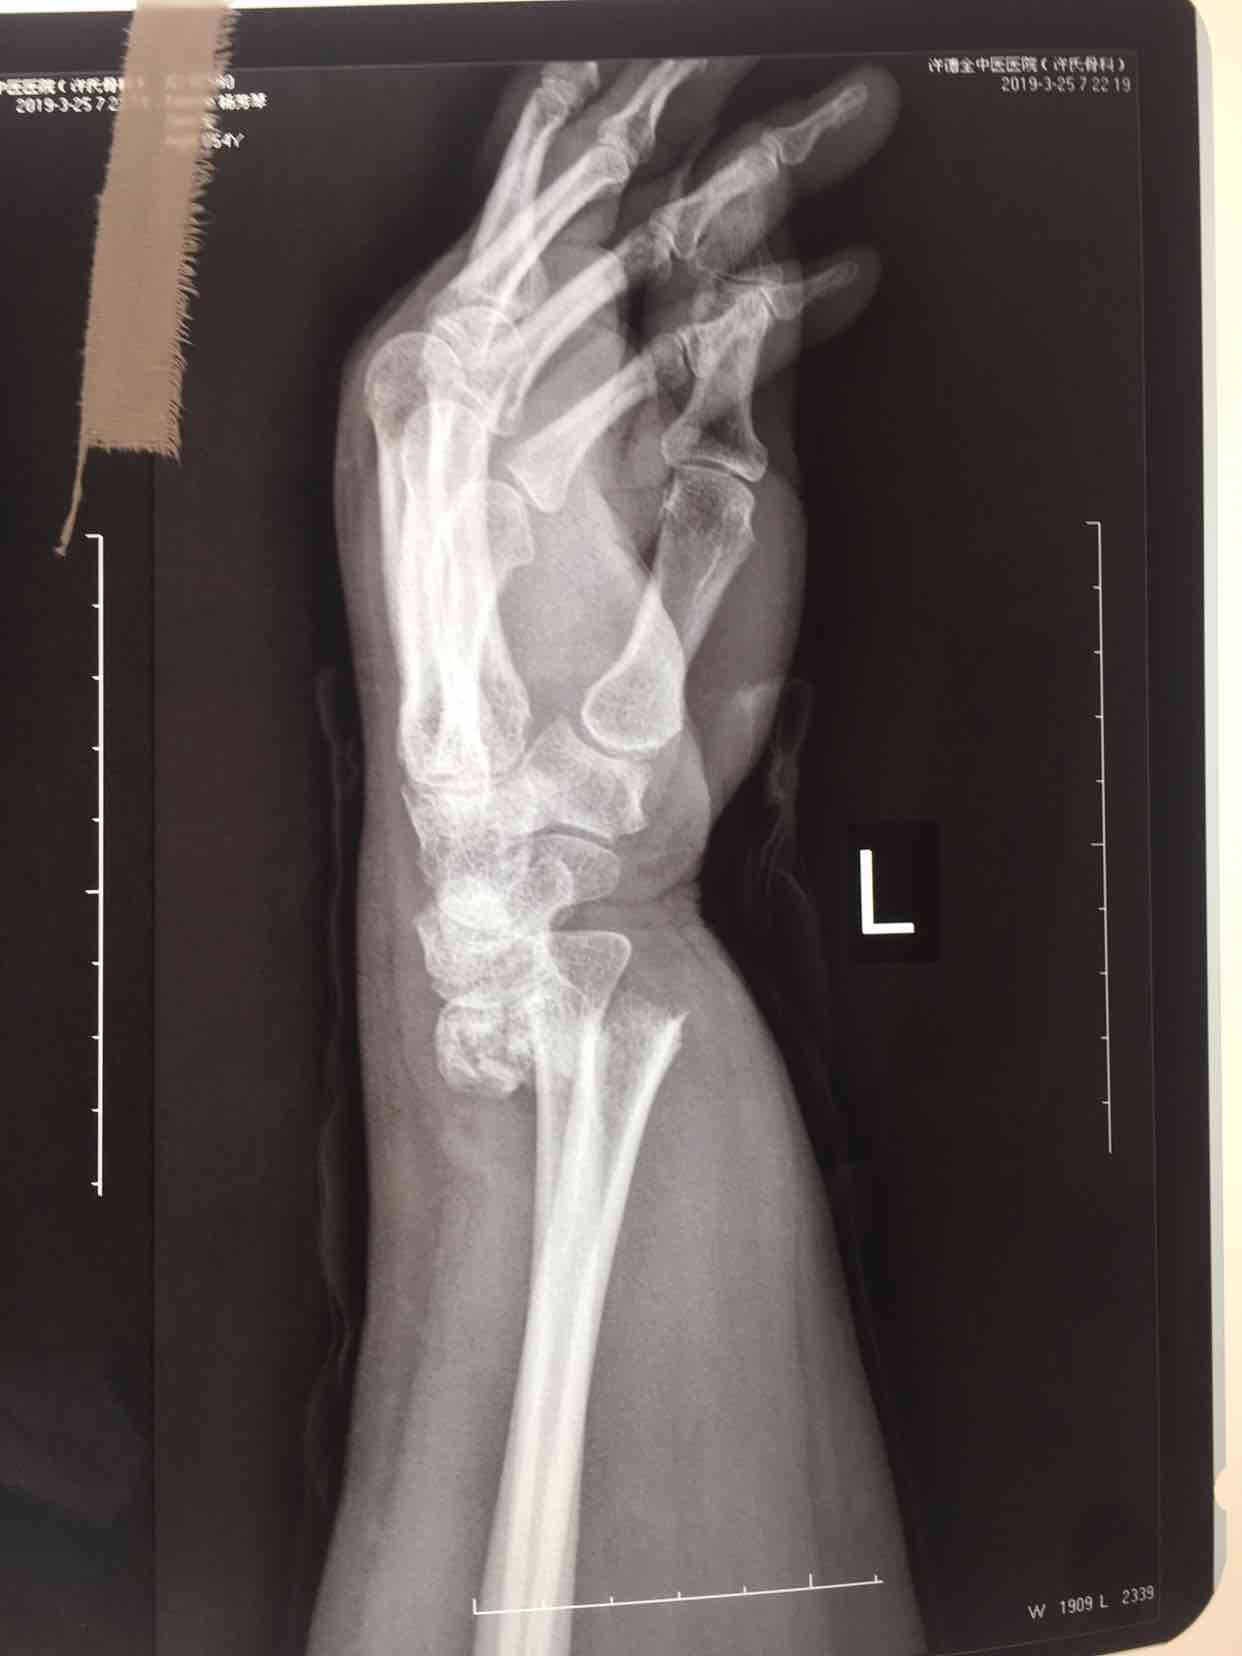

摔伤后左腕部肿痛,活动受限2小时入院。既往身体健康,无特殊不良嗜好。

生命体征平稳,心肺复未见异常。左腕部肿胀明显,畸形,局部皮温皮色基本正常,压痛及纵向叩击痛阳性,可及骨擦音及骨擦感,末梢血运感觉正常。

诊断尺桡骨远端粉碎性骨折在臂丛麻醉下行切复内固定术,术中克氏针临时固定,维持复位,术后石膏托固定,抗炎,消肿等处理。